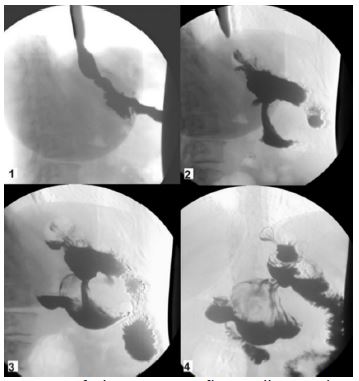

After multidisciplinary discussion and a Gastrografin swallow to understand the patient’s GI anatomy (Figure 3), she underwent a partial gastrectomy, sparing the previous gastric-ileal bypass (Figures 4). The histological examination observed a low-risk GIST (Figure 5), CD117/c-Kit negative, with R0 margins and the mitotic count was 1 mitosis/5 mmq.

Figure 3: Images of the Gastrografin swallow ordered in time sequence.